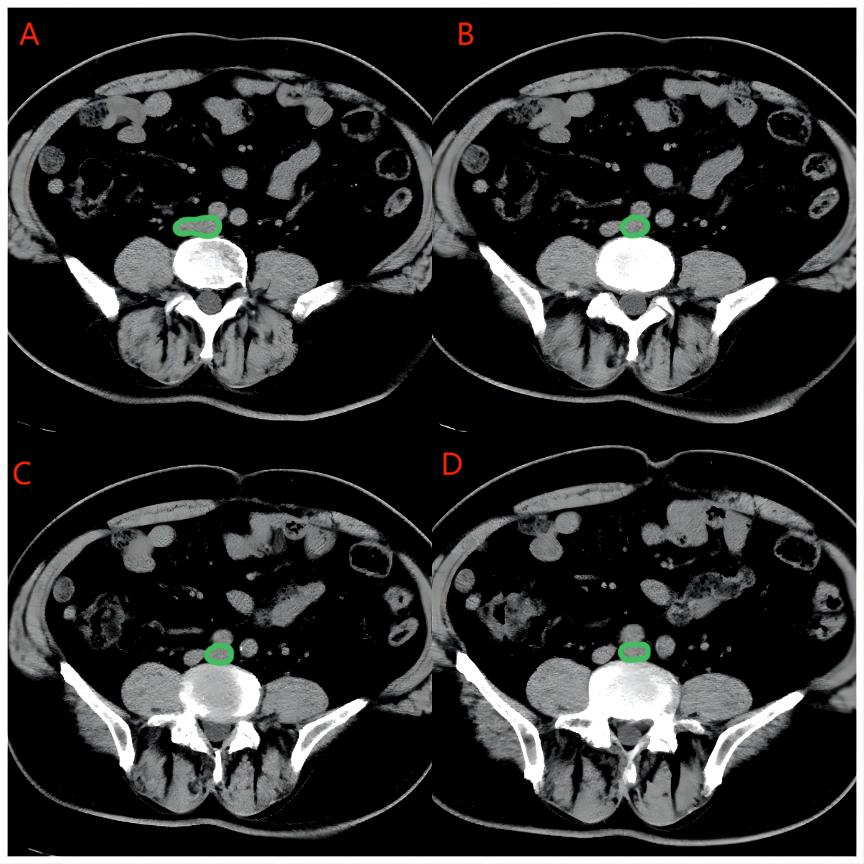

Refer to caption

Figure 3: Pic. A: Green mark is the bifurcation of the inferior vena cava, which is divided into left and right common iliac vein; Pic. B-D: The green mark is the left common iliac vein, which is visible between the surrounding right common iliac artery and the fifth lumbar spine, with no obvious compression stenosis.